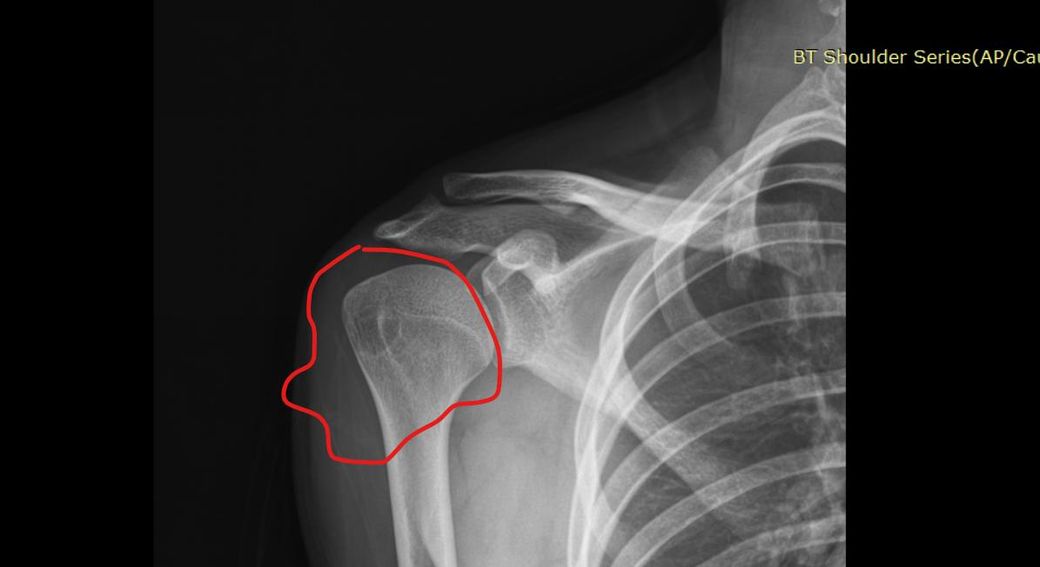

어깨 골수부종인가요 ? 뼈멍인가요 미세골절인가요 사고나고 뼈에 심하게 멍들었다고 했긴했습니다 전 잘모르겠어서 질문 해봅니다

• 1번 째 사진